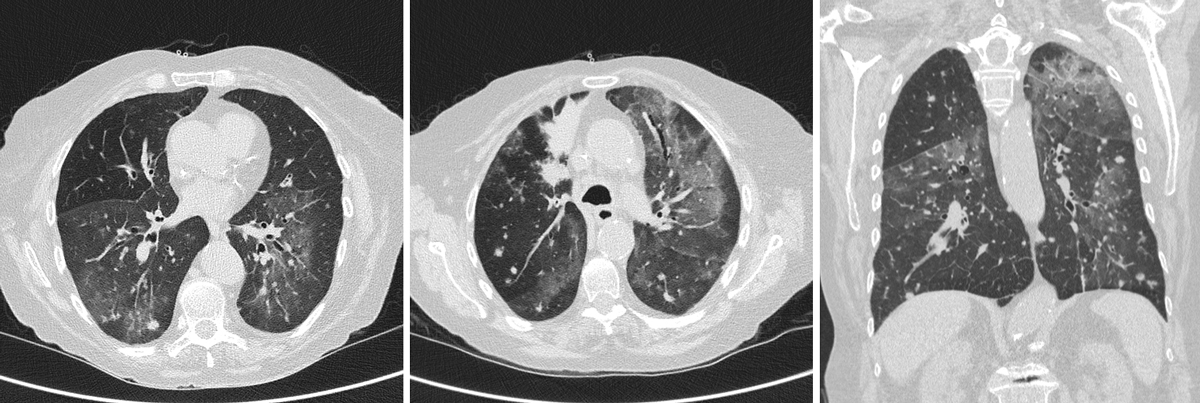

The patient was admitted to our hospital on 31 March 2020 with fever, cough and severe dyspnoea after 7 days of antibiotic treatment with levofloxacin for a suspected community-acquired pneumonia. On arrival, she was dyspnoeic with an oxygen saturation of 85% on room air. On clinical examination there was diffuse wheezing with bilateral crackles at the lung bases. Blood tests identified lymphopenia (0.5 × 109/l), elevated C-reactive protein of 62 mg/l and negative procalcitonin. We tested swabs for influenza A and B and respiratory syncytial virus, and urine for pneumococcus and Legionella pneumophila antigens, which were negative. Ultralow-dose chest computed tomography (CT) identified diffuse bilateral ground-glass opacities and multiple bilateral nodules (fig. 1). As the clinical and the radiological findings were strongly suggestive of COVID-19, we tested multiple nasopharyngeal swabs for SARS-CoV-2, which were negative. We completed the diagnostic work-up with serological and polymerase chain reaction (PCR) testing of stool and induced sputum samples, which were all negative.

Figure 1 Coronary and sagittal ultralow-dose chest CT scan showing diffuse bilateral ground-glass opacities and multiple bilateral nodules.

It is therefore of the outmost importance to remember the clinical reality of immunocompromised patients during the SARS-CoV-2 pandemic. P. jirovecii is a fungus causing pneumonia in humans and risk factors associated with this kind of infection are solid organ transplantation, HIV infection and administration of immune-modulatory drugs [6], whereas SARS-CoV-2 seems to affect patients regardless of their immune status [7]. Signs and symptoms present in both entities are fever, dry cough and dyspnoea. CT findings associated with P. jirovecii include diffuse bilateral ground-glass opacities, usually present in the mid to late stages of the disease, and giving a radiological appearance similar to SARS-CoV-2 [6, 8]. Both infections are associated with increased lactate dehydrogenase levels and lymphopenia [6, 8].

The radiological diagnosis of P. jirovecii can be problematic, since patterns of presentation are variable. It is important to stress that a differential diagnosis is key, not only because of the pandemic, but because we are still understanding the many faces of SARS-CoV-2 infection. Unfortunately the symptoms of SARS-CoV-2 are far from specific, as they are shared with many other frequent respiratory infections. Furthermore, this patient had already a difficult clinical picture involving the lungs (lung adenocarcinoma and COPD exacerbations), making it difficult to put things in the right perspective. The chest CT scan identified diffuse bilateral ground-glass opacities and multiple bilateral nodules. The clinical and radiological presentation of SARS-CoV-2 is common to different pathogens, so a better understanding of the CT scan and pathology findings will be key in developing more precise and reliable guidelines.